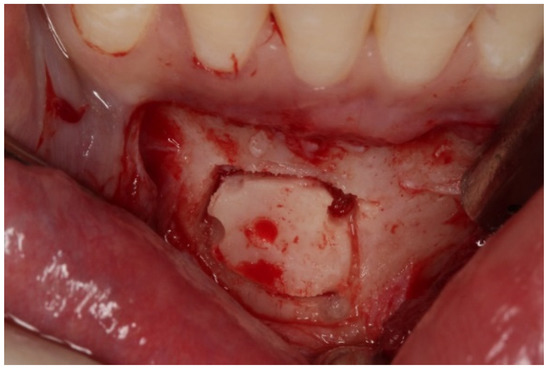

In all patients, the surgical procedure began with an intrasulcular incision and a papillae base incision on the anteroinferior teeth, from canine to canine (4.3 to 3.3). Auxiliary incisions were next made on distal aspects over the same teeth. The flap design took into account the emergence of the right and left mentonian nerves.

As for the bone block, it was based on the 5 mm rule, which instructs to leave at least 5 mm of bone tissue between the cut and surrounding anatomical landmarks, i.e., root apices of teeth 4.3 to 3.3, mental foramen, and mandibular basal bone [27,28]. The bone block was obtained with a piezoelectric scalpel (Piezosurgery®, Mectron® Medical, Carasco, Italy), because it allows exact cuts in hard tissues and its micro-vibrations do not damage adjacent tissues (Figure 3).

Figure 3.

Donor site of the mandible and chin block bone harvesting.